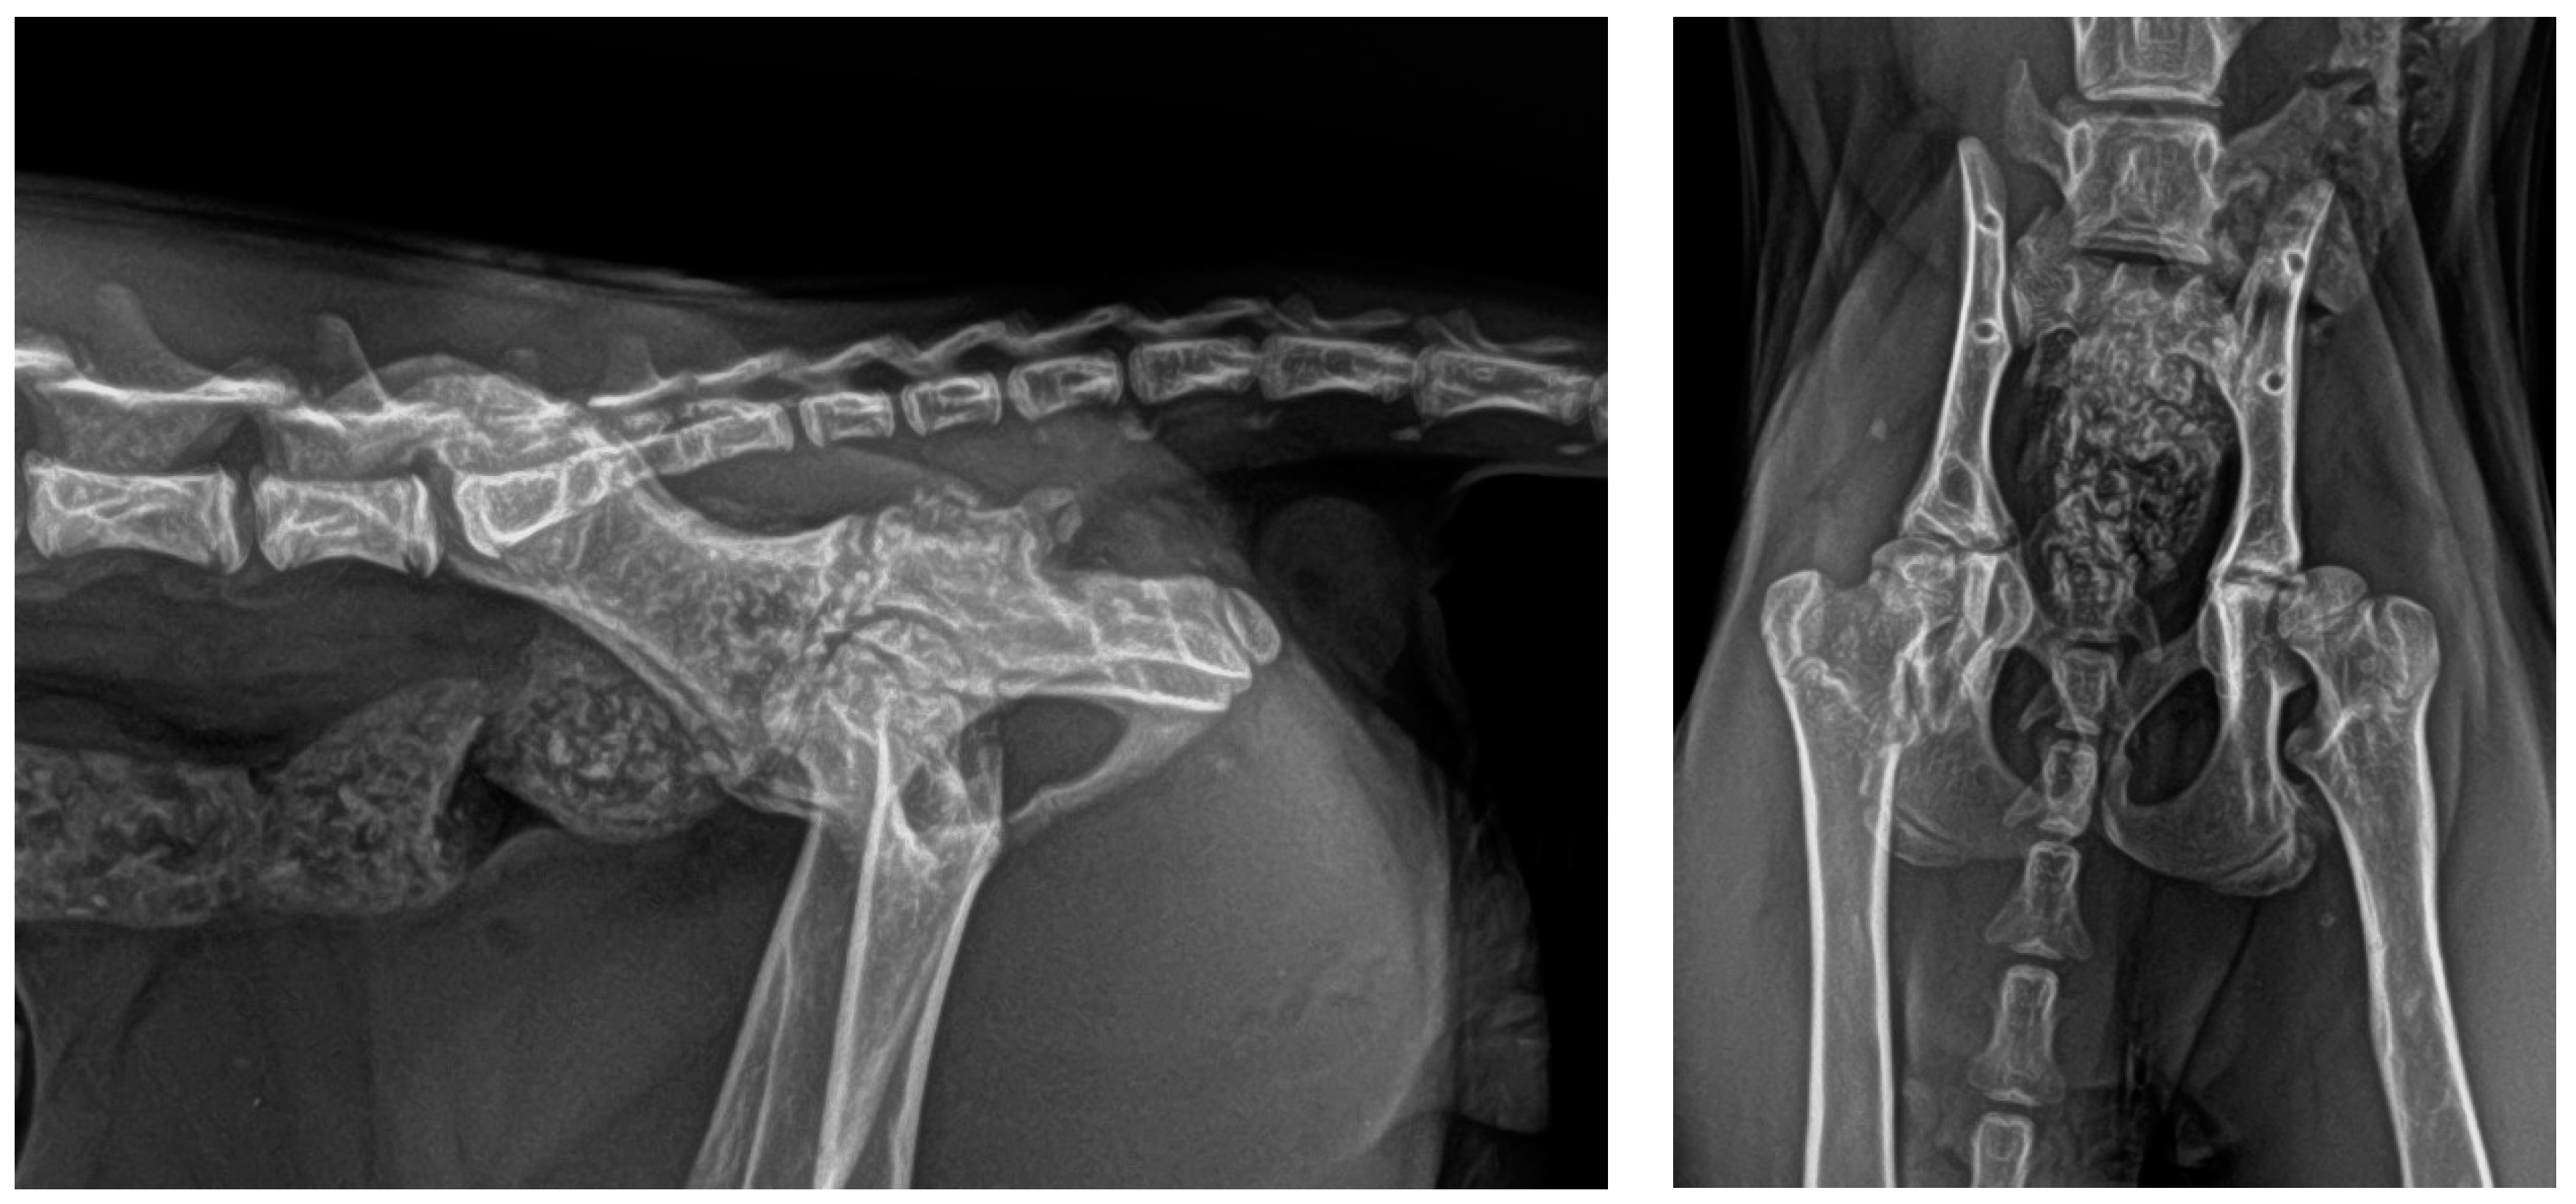

3. Results

2.3. Postoperative Care

2.4. Follow-Up